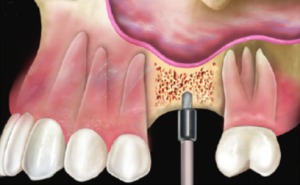

4. Quindi viene sollevata delicatamente la membrana, che ricopre internamente tutto il seno mascellare. |

5. Successivamente viene introdotto dell’osso artificiale all’interno del seno mascellare. |